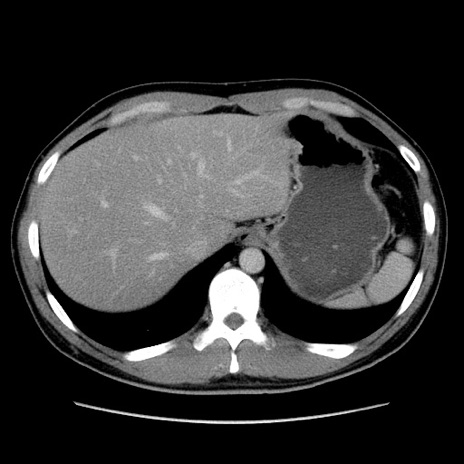

症例36(横断像)

【症例】20歳代 男性

【主訴】心窩部痛

【現病歴】今朝より上腹部痛あり。一旦軽快していたが再度出現したため救急要請。昨日夕に白身の魚を含む刺身を食べた。

【身体所見】BP 136/89mmHg、HR 74/min、BT 37.0℃、腹部:膨満、軟、心窩部に圧痛あり。反跳痛なし、筋性防御なし、腸雑音やや亢進あり。

【データ】WBC 17700、CRP 0.48